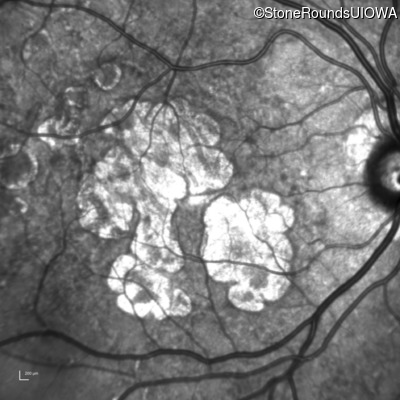

AR Stargardt Disease (IIA)

Age at visit: 59 years

This 59 year old man has noticed some blank spots near the center of his vision over the last 2 years.

Diagnosis & molecular findings

Disease Gene Allele 1 variant(s) Allele 2 variant(s) Inheritance mode

AR Stargardt Disease ABCA4 Leu2027Phe CTC>TTC IVS30+1321 A>G AR